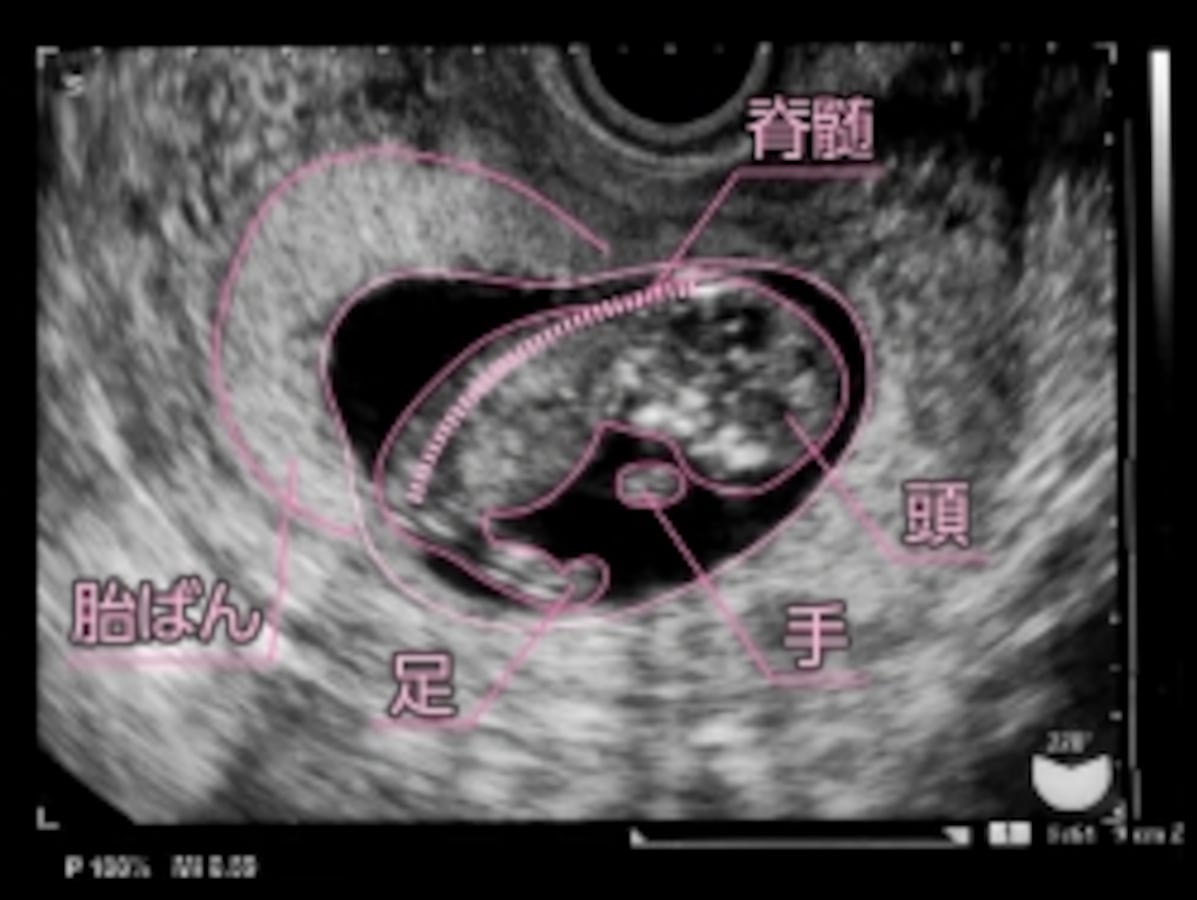

» 11 週 大き さ 平均 (99) 사진

11 週 大き さ 平均 (99) 사진